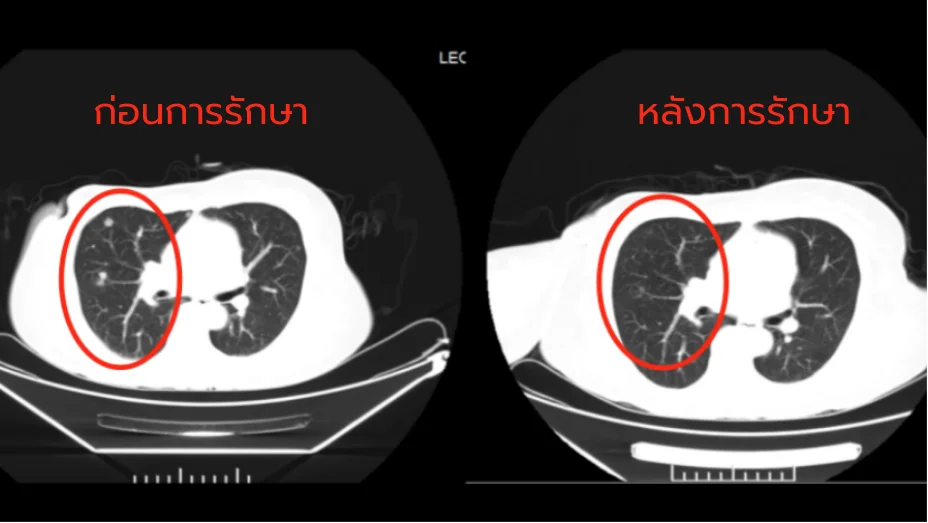

โรงพยาบาลมะเร็งสมัยใหม่กว่างใช้วิธีการรักษามะเร็งแบบใหม่ “การแพทย์ผสมผสานระหว่างจีนกับตะวันตก และการผ่าตัดแบบบาดแผลเล็ก” โดยใช้ทคนิค เช่น การรักษาแบบคีโมเฉพาะจุด การฝังรังสี การใช้มีดคังโป การจี้ด้วยคลื่นไมโครเวฟ มีดนาโน และการรักษาด้วยความเย็น ซึ่งจะมีการวางแผนการรักษาเฉพาะบุคคลตามสภาพร่างกายและความต้องการของผู้ป่วยด้วยเทคนิคการรักษาแบบบาดแผลเล็ก

การเปรียบเทียบประสิทธิภาพ

| อัตราการรอดชีวิต 5 ปี | 75% | 92% |

| อัตราการเก็บรักษาเต้านม | 30% | 85% |

| ผลข้างเคียงระดับ 3 ขึ้นไป | 35% | 8.7% |